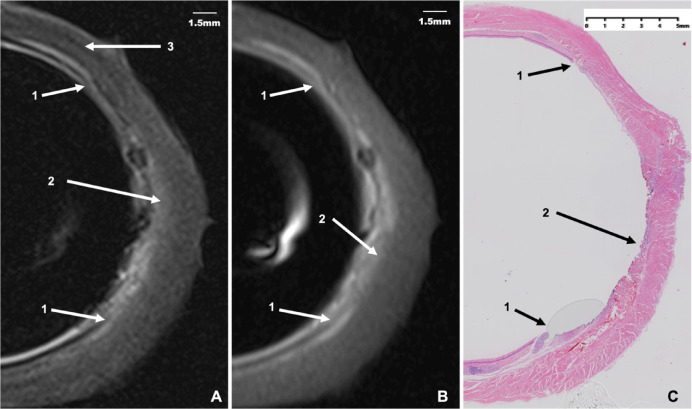

Endoscopic ultrasound (EUS) is the primary method for assessing the invasion depth of early esophageal cancer, though its capabilities are limited. To address this, we developed a compact endoluminal magnetic resonance (Endo-MR) coil equipped with a balloon and evaluated its imaging performance on pig esophagi. The inflatable balloon effectively maintains the esophageal morphology and reduces artifacts around the coil. Using T1-weighted and T2-weighted Endo-MR imaging, distinct esophageal layers, including the epithelial layer, lamina propria and muscularis mucosae, submucosa, muscularis propria, and adventitia, were identified, with superior contrast in T2-weighted images. Thermal injuries to the mucosa showed clear morphological correlation with Endo-MR images, enabling depth of invasion assessment via signal layer continuity. Compared to EUS, Endo-MR provided greater imaging stability in ex vivo environment (P < 0.01). These findings demonstrate that Endo-MR offers high spatial resolution and stable image quality, enabling detailed visualization of fine esophageal microstructures and small lesions, thus holding promising potential for clinical diagnosis.

内镜超声(EUS)是评估早期食管癌浸润深度的主要方法,但其能力有限。为了解决这个问题,我们开发了一种紧凑的腔内磁共振(Endo-MR)线圈,配备了一个气球,并评估了它在猪食管上的成像性能。充气球囊有效维持食管形态,减少线圈周围的伪影。通过t1加权和t2加权的Endo-MR成像,可以识别出明显的食管层,包括上皮层、固有层和粘膜肌层、粘膜下层、固有肌层和外膜,t2加权图像的对比度较好。粘膜热损伤与Endo-MR图像具有清晰的形态学相关性,可以通过信号层连续性评估浸润深度。与EUS相比,Endo-MR在离体环境下具有更高的成像稳定性(P